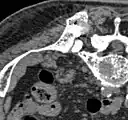

- Vues au scanner d'une ablation aux micro-ondes

Avant l'ablation : crête supérieure arrière de l'ilion, avec une métastase ostéolytique (diam. environ 2 cm, flèches)

Avant l'ablation : crête supérieure arrière de l'ilion, avec une métastase ostéolytique (diam. environ 2 cm, flèches) A-Pendant l'ablation, l'électrode micro-onde est directement insérée dans la métastase. B-En fin d'ablation, un mélange de ciment pour os et de sulfate de baryum est injecté dans l'espace vide créé.

A-Pendant l'ablation, l'électrode micro-onde est directement insérée dans la métastase. B-En fin d'ablation, un mélange de ciment pour os et de sulfate de baryum est injecté dans l'espace vide créé. Après ablation, la répartition du ciment dans l'espace vide est visible.

Après ablation, la répartition du ciment dans l'espace vide est visible.